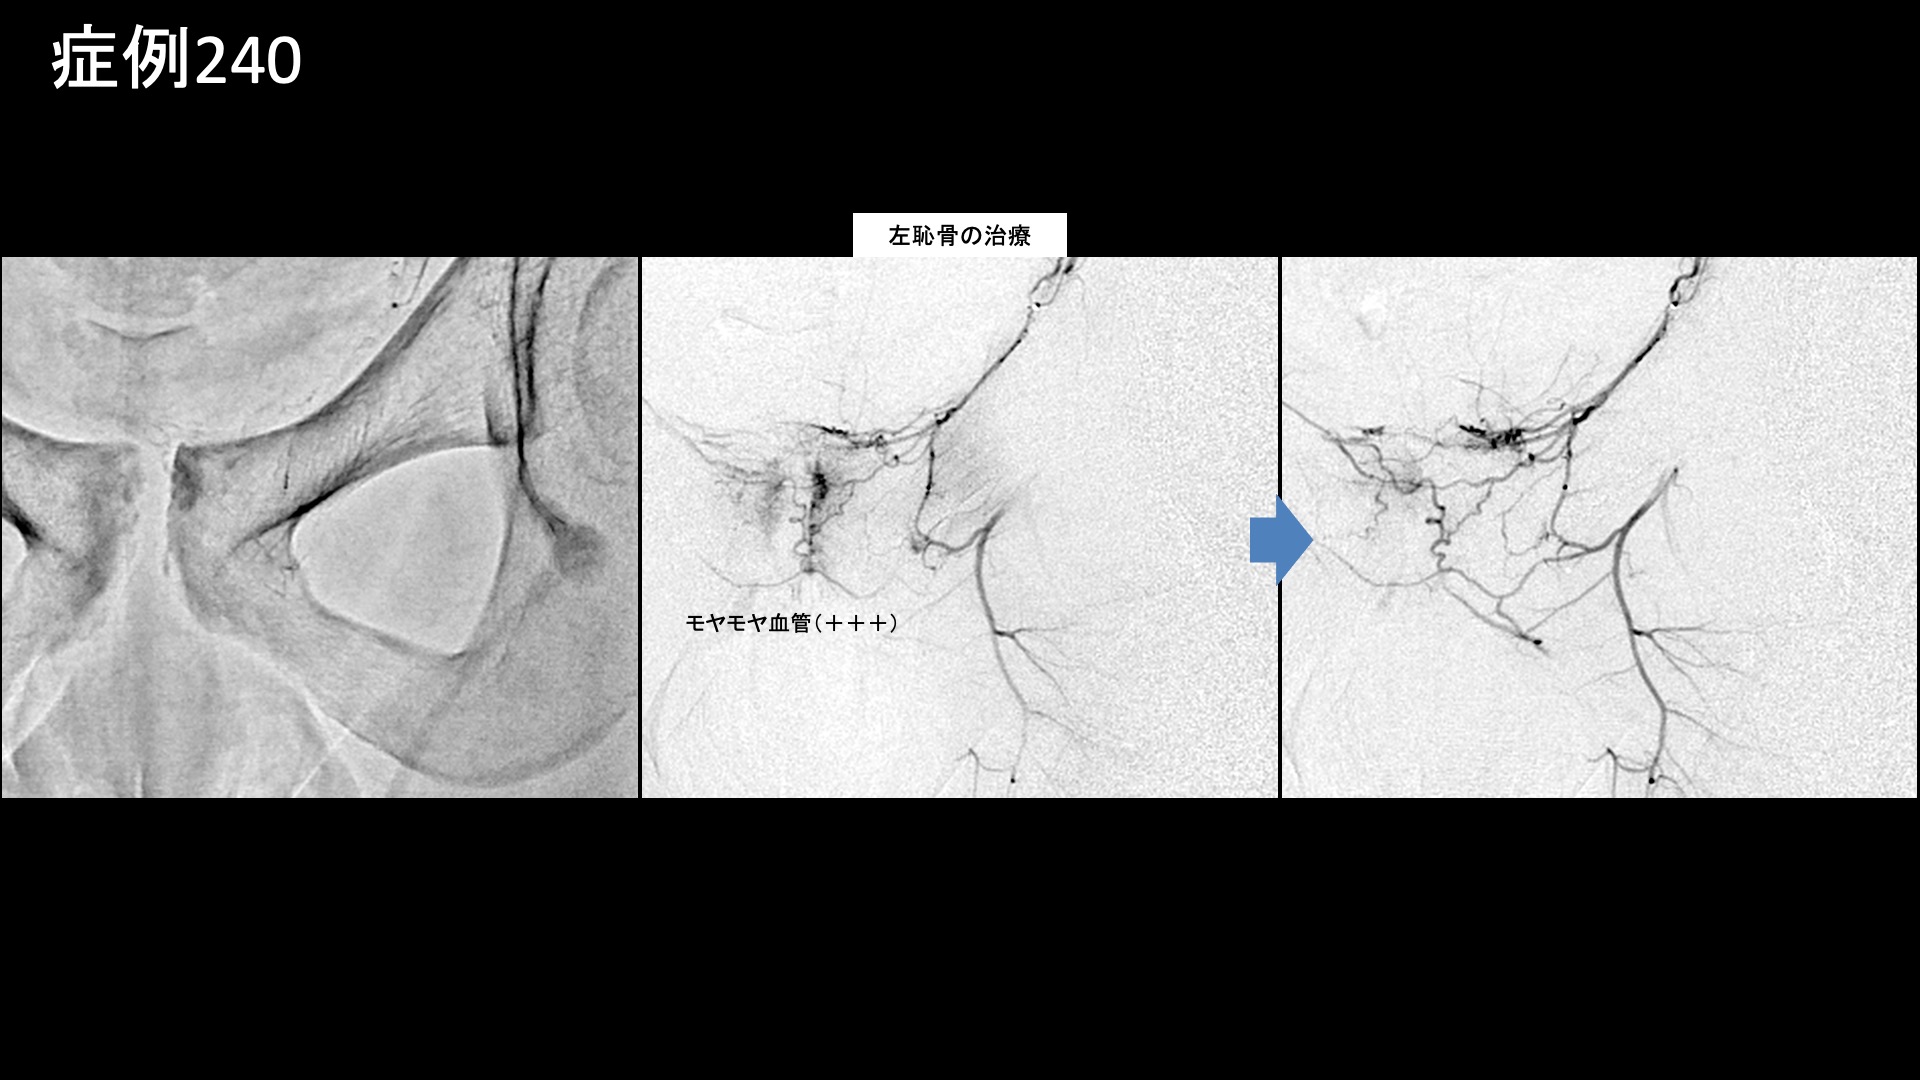

股:変形性股関節症など 【10代:男性】恥骨が痛くて走れない、スポーツが原因で生じた恥骨結合炎に対するモヤモヤ血管治療(恥骨結合炎) 2025.09.26 鴨井院長による動画解説 受診までの経過 スポーツが原因で、半年前から恥骨が痛むようになりました。日常生活では問題ないものの、ランニングで痛み走れなくなってしまいました。キック動作でも悪化しました。下腹部痛はなく、あくまでも恥骨に限局した痛みでした。MRI検査の結果、恥骨結合炎と診断されました。体外衝撃波治療や鍼治療を受けましたが改善しませんでした。十分安静療養をしてきたにもかかわらず、いつまでも治らないことから当院を受診されました。 診察時の所見 恥骨結合に一致して圧痛が見られましたが、少し広範囲に及んでいました。レントゲンでは恥骨結合が開大しており、結合面の骨表層は不整でした。MRI検査では、脂肪抑制T2強調画像において、恥骨結合周囲に高信号を明瞭に認めました。画像所見からは強い炎症が示唆され、日常生活で症状を生じても不思議ではない程度でした。治療適応と判断し、モヤモヤ血管(病的新生血管)に対する運動器カテーテル治療(微細動脈塞栓術)を受けていただきました。 治療の所見 血管造影を行うと、恥骨結合周囲に一致してモヤモヤ血管が濃染像として描出されました。治療後は画像上速やかに消失しました。その他複数個所の治療を行い終了しました。尚、治療時には恥骨結合における再現痛も確認できました。 *再現痛とは、薬液投与時に普段の痛みが一定程度再現される現象です。責任血管の同定のための参考とします。 治療後の経過 治療後2週間、激しい動作は控えていたため、まだ良くなっているかどうかはわかりませんでした。恥骨における圧痛は過敏さが無くなったものの、まだ比較的広範囲に認められました。治療後1ヶ月、走った後に少し違和感があるものの、ダッシュしてみても痛まなくなりました。患部を自分で押してみましたが痛くありませんでした。診察では、圧痛は強度・範囲とも大幅に減っていました。経過良好でした。その後、下半身の筋力トレーニングをした際に痛みが強くなることはあったものの、順調に経過し、治療後6ヶ月時点でもほとんど痛みなく過ごせているとのことでした。典型的な恥骨結合炎の症例でした。早期から改善し、再発なく経過されていて何よりでした。 【70代:男性】夜間痛がその日のうちに改善!強い炎症を伴った変形性膝関節症に対する運動器カテーテル治療(変形性膝関節症) 前の記事 【80代:男性】火が出るような痛みに襲われ夜も寝られず・・発症1ヶ月の頭部/顔面に生じた帯状疱疹後神経痛(帯状疱疹後神経痛) 次の記事